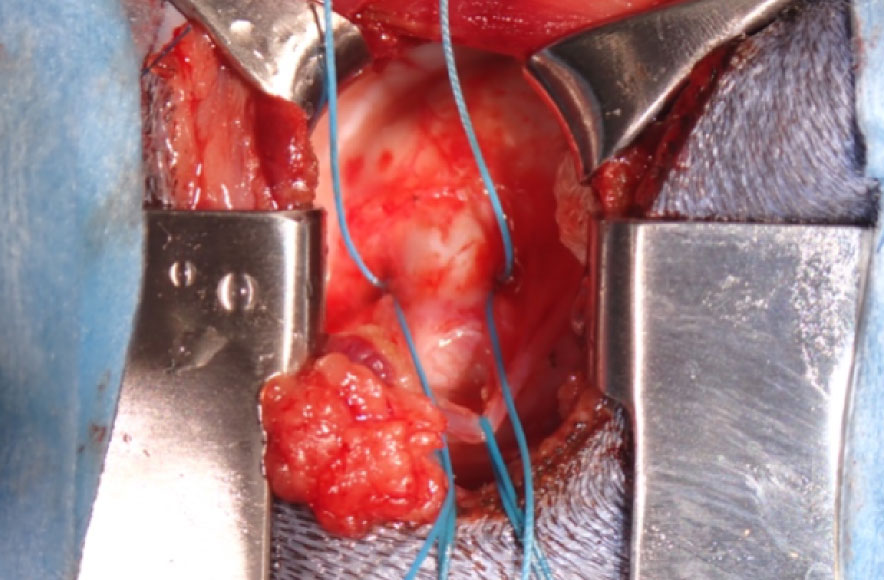

手術後

| 犬種 | マルチーズ 11歳 5kg |

| 治療と経過 | 術後には僧帽弁の逆流が大幅に減少あるいは消失することで、心臓への負担が軽減され術前と比較して心臓サイズが縮小します。多くの症例で術後1ヵ月以内に今まで飲んでいた循環器系の内服薬が不要となります。術後3ヵ月までは、術後血栓症のリスクがあるため抗血栓治療が必要となります。 |